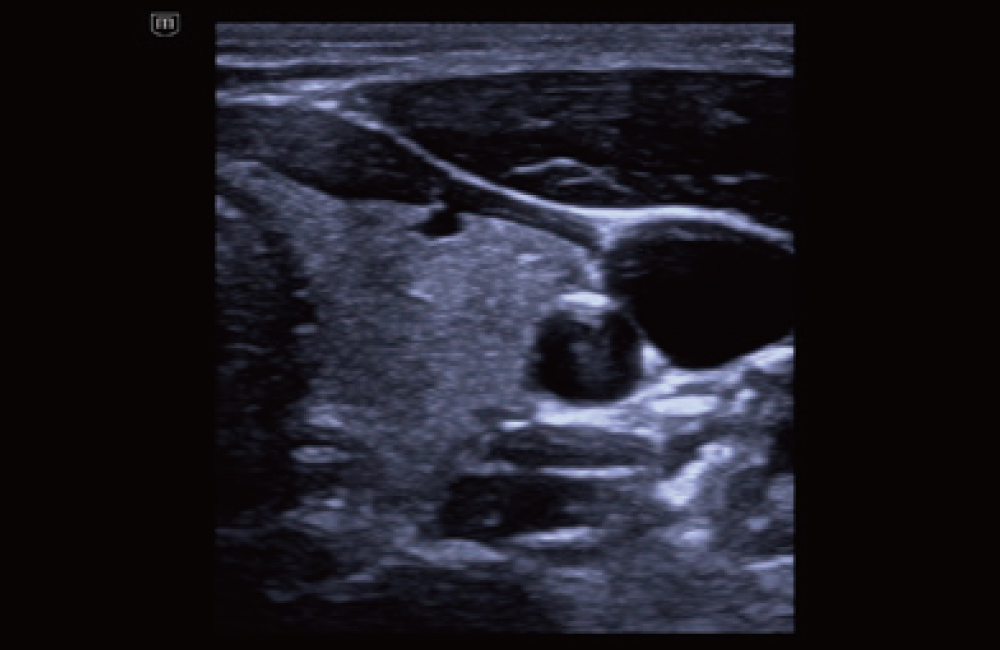

Schildklier met iTouch+